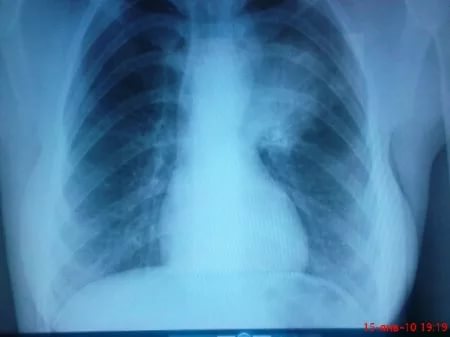

О чем свидетельствуют результаты рентгенографии и КТ

Рентгенография для диагностики пневмонии

При получении результатов рентгенографического исследования у больного обнаруживаются грубые изменения в легких.

Отличительной чертой лобарной казеозной пневмонии является затемнение большей части легкого. В некоторых случаях темной может быть вся доля.

В начале заболевания затемнение однородное, но по мере прогрессирования начинают появляться светлые участки с расплывчатыми контурами (при неспецифической пневмонии контуры четкие). В светлых участках видны полости распада. На компьютерной томографии в пораженной доле легкого просматриваются просветы расширенных бронхов. Пораженная доля легкого уменьшается в результате потери эластичности.

Рентгенограмма у людей, страдающих лобулярной казеозной пневмонией, показывает крупные очаговые затемнения неправильной формы с расплывчатыми контурами. Компьютерная томография позволяет увидеть множество полостей распада.